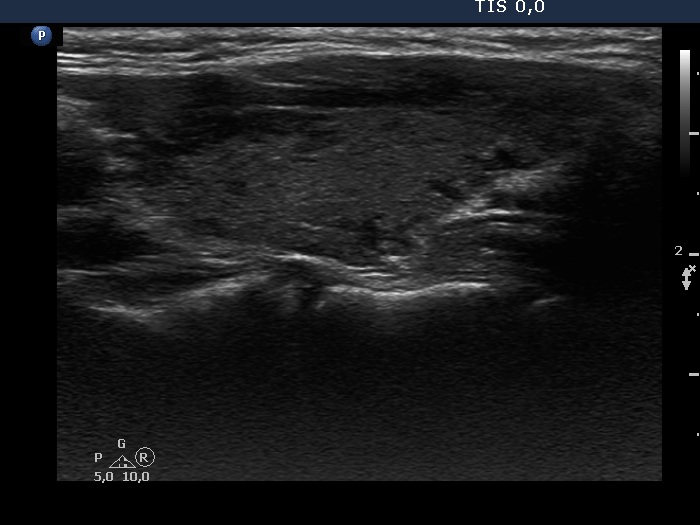

Discrete lesion or nodule in Hashimoto's thyroiditis - case 11 (1241) (ultrasonographic picture 6)

Right lobe, longitudinal scan